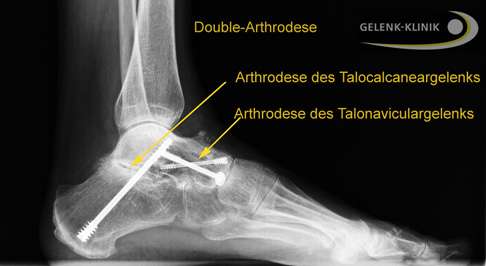

Nachdem sich der Fußchirurg über einen Hautschnitt Zugang zum Gelenk verschafft hat, entfernt er zunächst den kompletten Knorpel im Talocalcanear- und im Talonaviculargelenk. Dann bereitet er die Knochenflächen so vor, dass sie optimal zusammenpassen. Manchmal wird dafür ein Teil des Knochens entfernt oder geglättet. Im nächsten Schritt fixiert der Operateur die Knochen in der gewünschten Position. Dies kann mithilfe von Schrauben, Platten, Nägeln oder Drähten erfolgen, die die Knochen stabil aneinander halten.

Die Double-Arthrodese ist ein chirurgischer Eingriff, bei dem zwei benachbarte Fußgelenke dauerhaft versteift werden, um Schmerzen zu lindern und die Stabilität des Fußes zu verbessern. Sie umfasst die wichtigsten Anteile des unteren Sprunggelenks: das Gelenk zwischen Sprungbein und Kahnbein (Talonaviculargelenk) und das Gelenk zwischen Sprungbein und Fersenbein (Talocalcaneargelenk).